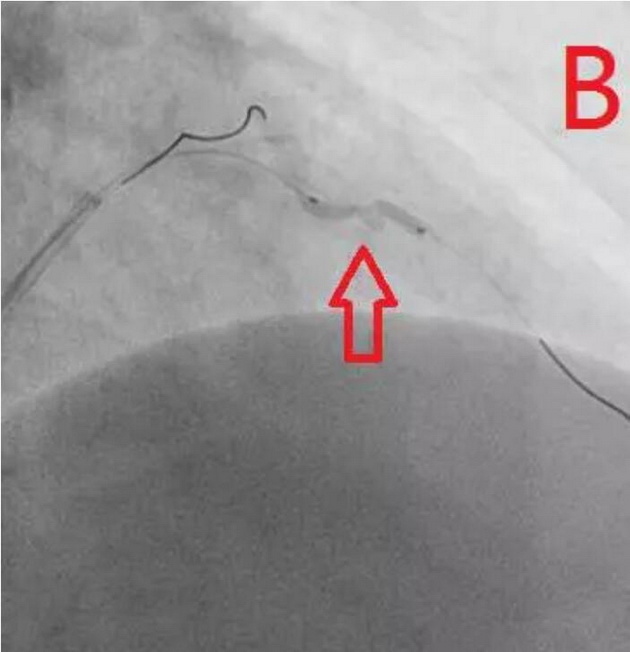

患者为77岁女性,因冠心病进行冠状动脉介入治疗,造影发现冠状动脉前降支不仅闭塞(图A),而且伴有钙化。通过不懈的努力,将闭塞的血管打开,但钙化处球囊无法将病变充分扩张(图B),意味着无法通过植入支架来维持血管管腔。于是采用血管内超声对病变处进行检测,显示病变处存在严重的360度环形钙化(图C、D)。